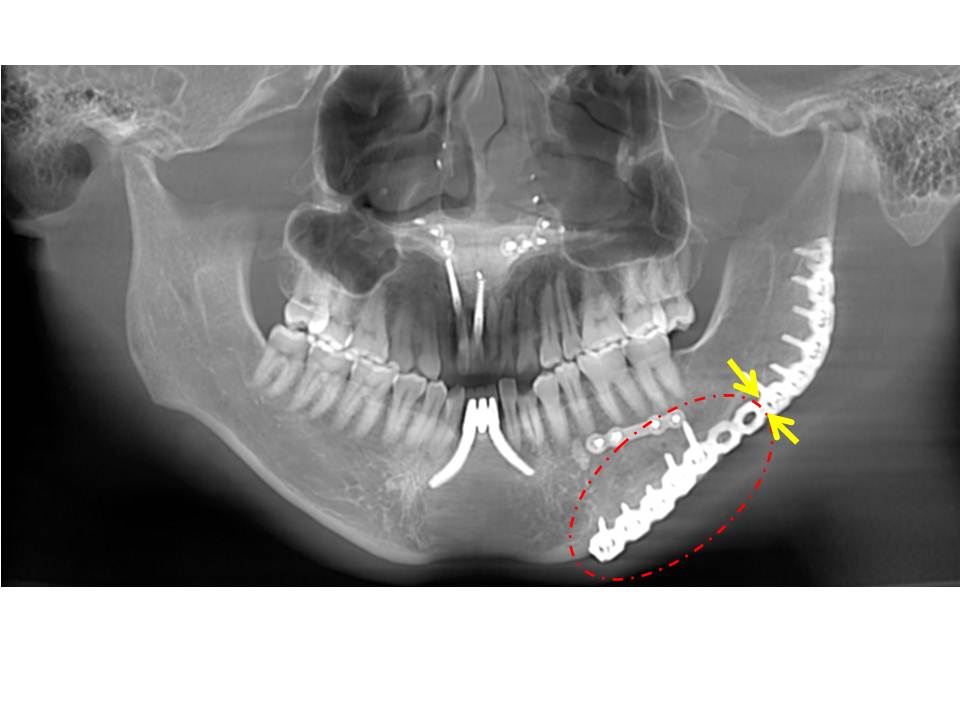

図25 顔面骨骨折の部位別頻度(関西医科大学救命救急センター、1987〜1996) 図26 眼窩吹き抜け骨折(mri像) 図27 頬骨骨折(3d−ct像) 図28 ルフォー型骨折 図29 下顎骨骨折(3d−ct像) 骨折の分類 原因 外傷性骨折⇄病的骨折 軟組織損傷 単純骨折⇄複雑骨折 「バラバラになったか」ではない 離断の程度 完全骨折(遊離)⇄不完全骨折(亀裂) 骨折線 単線骨折⇄複線(多線、粉砕)骨折 外力の作用部位 直達骨折⇄会達骨折 オトガイ打って筋突起 時間 新鮮骨折⇄陳旧骨折下顎骨骨折は, 骨折部位により, オトガイ部, 骨体部, 下 顎角部, 下顎枝部, 筋突起および関節突起部に分類される (図1) 4 ).歯槽骨に限局する骨折は, 歯槽骨骨折として別 に分類される.下顎骨骨折様態として, 完全骨折か不全骨